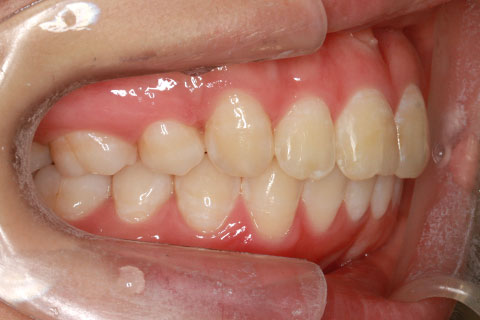

ハーフリンガル矯正4(上の歯のみ舌側矯正で治療)

治療前

治療後

- 年齢・性別

- 23歳女性

- 治療期間

- 2年0ヶ月

- 抜歯

- 上下4番抜歯

- 治療費

- 110万円

- 備考

- マルチブラケットを用いた矯正治療

- 治療内容

- 施術の副作用(リスク)

- 表側矯正と比較して、前歯のラビッティング(舌側傾斜)を起こしやすい。